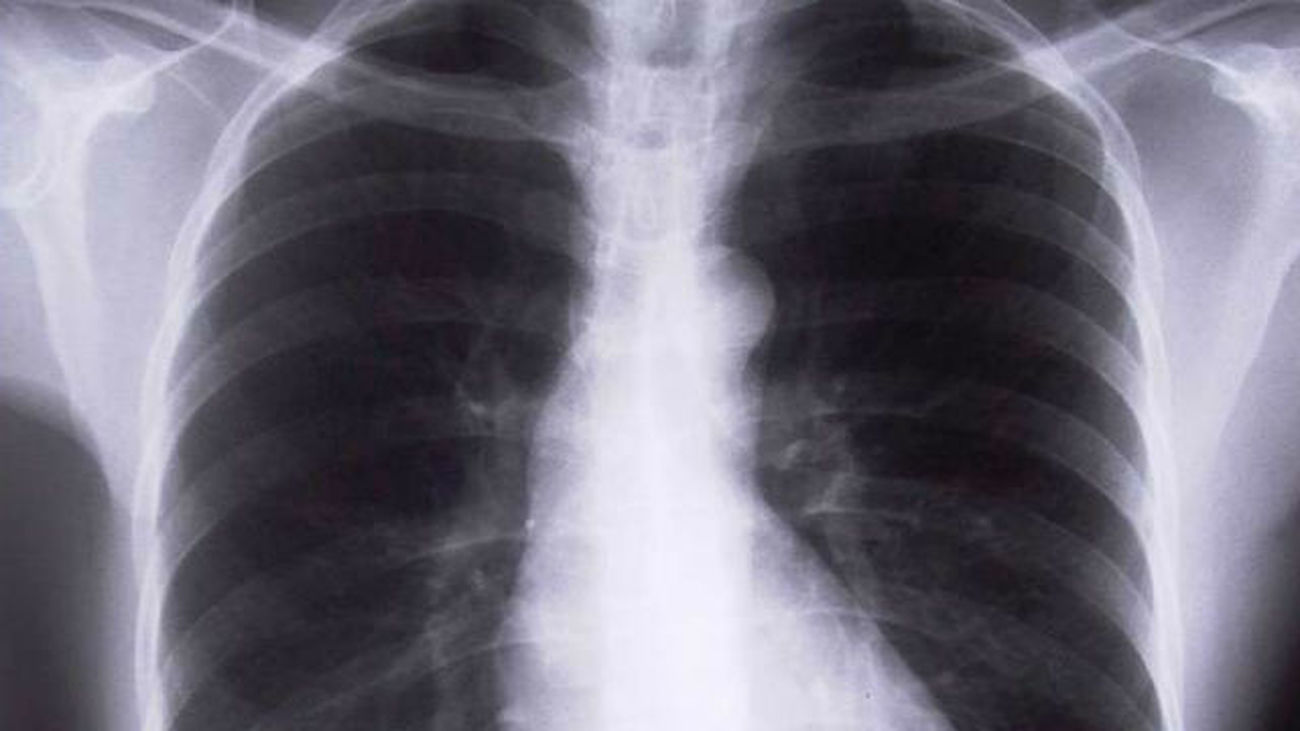

El carcinoma de pulmón, el tipo de cáncer que más muertes causa en el mundo, tiene los días contados